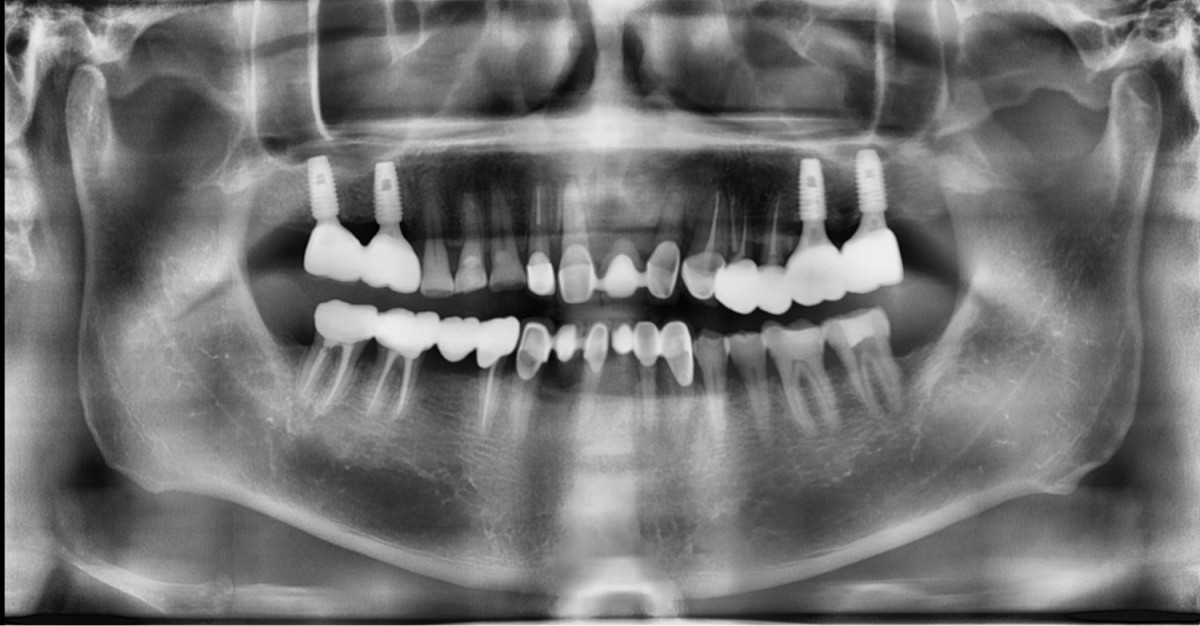

A 57-year-old male patient recently underwent

implant restoration on the maxillary right molar. This time, he is scheduled to

proceed with the left molars. (ARUM implant system)

▲2 implants were placed. ArumDentistry NB1 5*10 (30Ncm) in the 1st molar and 5*10 (10Ncm) in the 2nd molar.